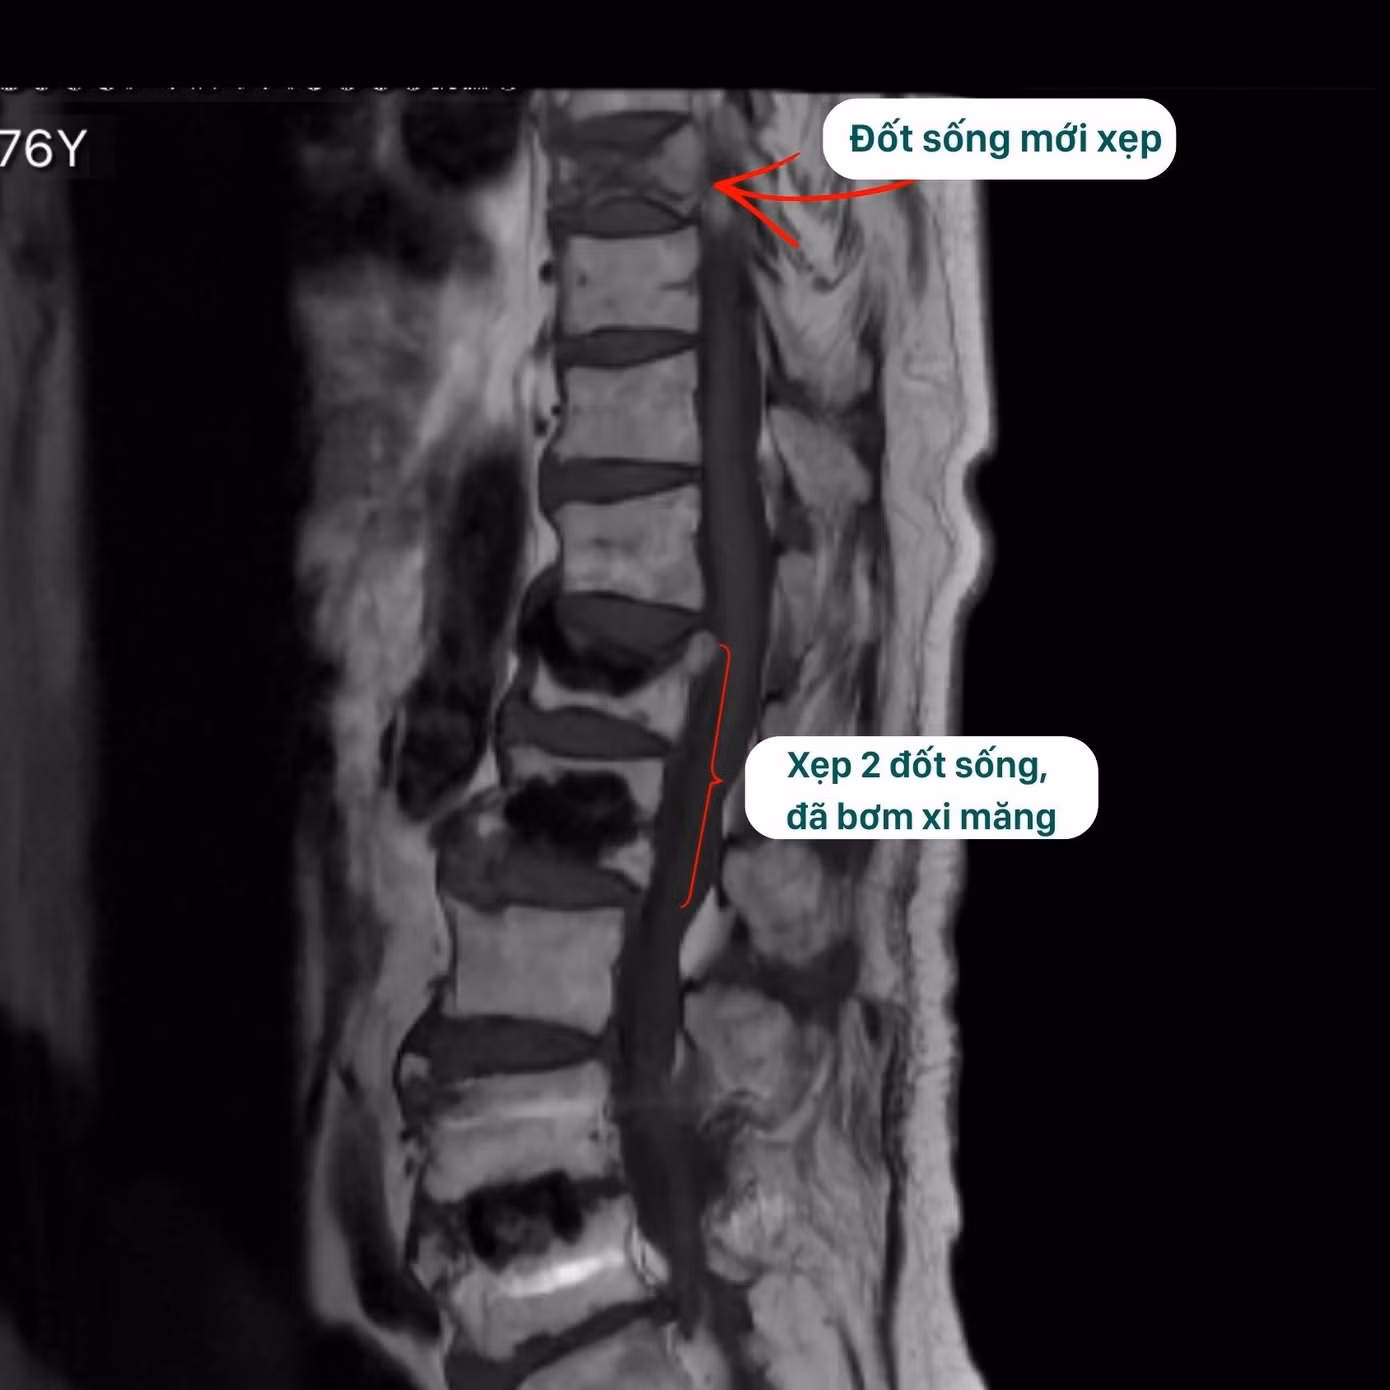

Phim chụp tình trạng xẹp nhiều đốt sống do loãng xương

Điển hình là trường hợp bệnh nhân D (76 tuổi), trước đó bị lún xẹp 2 đốt sống và đã được can thiệp bơm xi măng sinh học tại cơ sở y tế địa phương. Sau điều trị, tình trạng đau cải thiện, vận động ổn định. Tuy nhiên, thời gian gần đây người bệnh xuất hiện đau lưng dữ dội, giảm khả năng vận động, phải di chuyển bằng xe lăn và phụ thuộc trong sinh hoạt. Khi đến BVĐK Hồng Ngọc thăm khám, kết quả chụp MRI ghi nhận xẹp mới đốt sống T9.